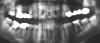

shelvi Опубликовано 6 июля, 2008 Поделиться Опубликовано 6 июля, 2008 Уважаемые врачи! Объясните есть ли какие-то технологии современной стоматологии в г. Москве, позволяющие сохранять такие зубы как 3-й нижний справа на картинке. Зуб не шатается и не болит. А если есть то порекомендуйте врача, пожалуйста. Я понимаю, что такое если и лечится, то без 100%-й гарантии на успех. Про удаление и имплантацию меня уже подробно проконсультировали, но все же хочется оттянуть эту процедуру на неопределенный срок. Ссылка на комментарий

Гость Vini Vidi Vici Опубликовано 6 июля, 2008 Поделиться Опубликовано 6 июля, 2008 Уважаемые врачи! Объясните есть ли какие-то технологии современной стоматологии в г. Москве, позволяющие сохранять такие зубы как 3-й нижний справа на картинке. Зуб не шатается и не болит. А если есть то порекомендуйте врача, пожалуйста. Я понимаю, что такое если и лечится, то без 100%-й гарантии на успех. Про удаление и имплантацию меня уже подробно проконсультировали, но все же хочется оттянуть эту процедуру на неопределенный срок.К сожалению, вылечить такой зуб терапевтически невозможно: деструкция костной ткани достигла критической отметки. Она распространяется не только на околоверхушечный, но и межкорневой периодонт-такие изменения обратному развитию не подвержены. Удаляйте лучше, пока нет обострения-в фазе обострения удаление зуба будет для Вас более проблемным. Учтите ещё и то, что киста будет увеличиваться в размерах и может привести к перелому нижней челюсти в этом отделе. Ссылка на комментарий

cactus Опубликовано 7 июля, 2008 Поделиться Опубликовано 7 июля, 2008 это называется 36й зуб.имхо шансов у него нет никаких А чем по вашему отличается большая деструкция от маленькой? Только одним - количеством внутриканальных микроорганизмов. "Зуб не шатается" - дает шанс на отсутсвие сообщения с полостью рта и соотвтсвено на отсутсвие истинного периопоражения. А уж истинное эндо - лечится стандартно. С предсказуемым результатом. Ссылка на комментарий

Bier Опубликовано 8 июля, 2008 Поделиться Опубликовано 8 июля, 2008 А чем по вашему отличается большая деструкция от маленькой? Только одним - количеством внутриканальных микроорганизмов. "Зуб не шатается" - дает шанс на отсутсвие сообщения с полостью рта и соотвтсвено на отсутсвие истинного периопоражения. А уж истинное эндо - лечится стандартно. С предсказуемым результатом.я считаю, что тут есть сообщение с полостью рта, через область фуркации. Ссылка на комментарий